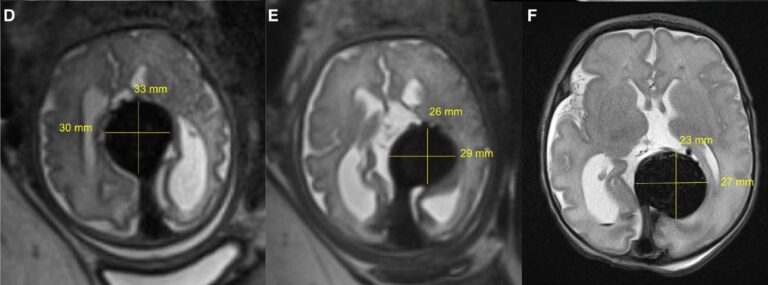

Сканування головного мозку немовляти, яке показує розмір аномалії, коли вона зменшується, зліва: до емболізації, одразу після та одразу після народження немовляти. Фото: Орбах та ін., Інсульт, 2023